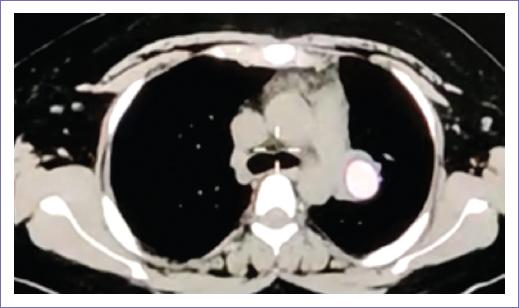

Figure 1 Axial computed tomography. Mediastinal window showing a tumor in the right upper lobe bronchus, which was resected 16 years ago.

A 31-year-old female with no family history, and with a history of cystic mature teratoma in the right ovary and right oophorectomy in 2004, underwent a right superior lobectomy for atypical carcinoid in 2007 (Fig. 1). In 2021, she was diagnosed with hypothyroidism, without other relevant medical history. In October 2021, she presented with non-threatening hemoptysis, cough, mild chest pain, and a history of prior pneumonia. Bronchoscopy revealed a well-rounded, well-vascularized lesion occluding the bronchus of the left upper lobe; biopsies were taken, and histopathology confirmed a neuroendocrine tumor. During the procedure, a cryoresection was performed, achieving 50% bronchial patency. Immunohistochemistry stains were positive for synaptophysin, with a Ki-67 proliferation index of < 5%.